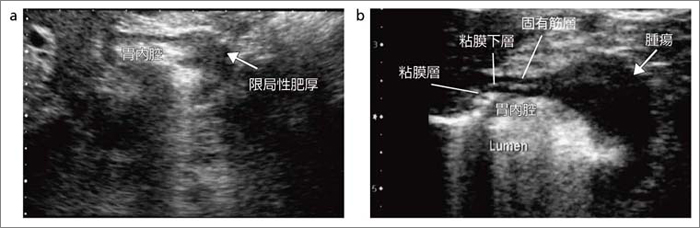

もらって嬉しい出産祝い 消化器内科 第28号(Vol.4 No.3,2022)特集:体外式超音波による 医学一般

消化器内科 第28号(Vol.4 No.3,2022)特集:体外式超音波による,

消化器内科 第28号(Vol.4 No.3,2022)特集:体外式超音波による, 消化管エコーの最新動向 - 新。超音波診断 Vol.03 - 東芝,

消化管エコーの最新動向 - 新。超音波診断 Vol.03 - 東芝, 腹部超音波検査(腹部エコー検査) | 医療法人 木村医院,

腹部超音波検査(腹部エコー検査) | 医療法人 木村医院, 消化管エコーの最新動向 - 新。超音波診断 Vol.03 - 東芝,

消化管エコーの最新動向 - 新。超音波診断 Vol.03 - 東芝, 消化器内科 第18号(Vol.3 No.5,2021)特集:食道胃接合部癌の診断